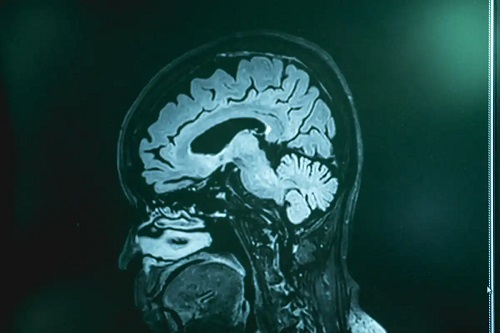

După cum indică manualele MSD, această boală poate fi confirmată prin puncție lombară (și analiza ulterioară a lichidului cefalorahidian), precum și prin biopsie cerebrală. Medicii efectuează aceste teste persoanelor cu simptome de naegleroză care au fost în contact cu apă proaspătă netratată în ultimele zile.

Testele imagistice (tomografie computerizată și imagistica prin rezonanță magnetică) nu detectează boala, dar pot exclude alte posibile probleme de sănătate. Medicii efectuează culturi sau analize genetice în căutarea genomului amibei.